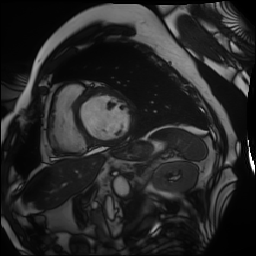

Synthetic Data Samples

Figure: Synthetic data generated by StyleGAN2-ADA for ACDC (top) and FIVES (bottom) datasets. Left to right: first 3 are original images, next 3 generated using 5% real data, last 3 using 10% real data.